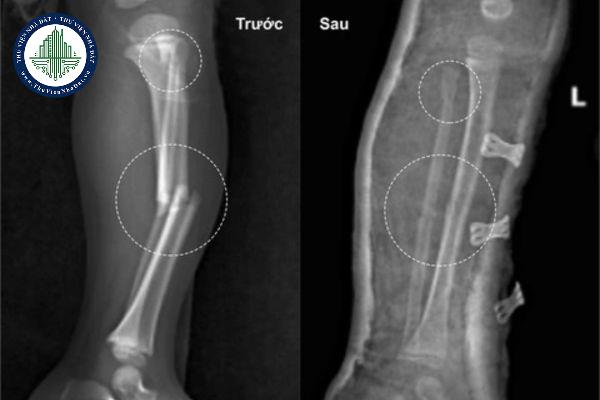

Nhân viên bị tai nạn gãy chân giải quyết như thế nào cho thỏa đáng?

Theo kinh nghiệm của anh chị thì trường hợp nhân viên bị tai nạn gãy chân phải nghỉ ở nhà nhiều tháng liên tiếp (không thuộc nghỉ ốm đau dài ngày) và thường xuyên phải đi tái khám tại cơ sở y tế. Công ty cần làm gì để đảm bảo quyền lợi cho họ?